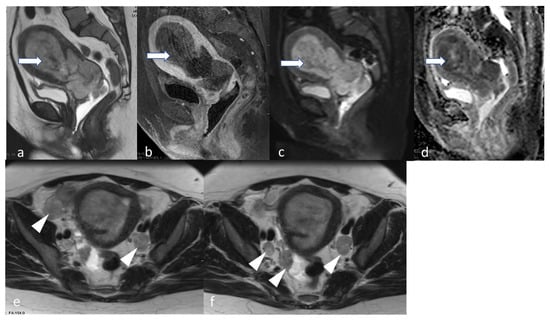

5.3. Magnetic Resonance Imaging (MRI)

- Maheshwari, E.; Nougaret, S.; Stein, E.B.; Rauch, G.M.; Hwang, K.-P.; Stafford, R.J.; Klopp, A.H.; Soliman, P.T.; Maturen, K.E.; Rockall, A.G.; et al. Update on MRI in Evaluation and Treatment of Endometrial Cancer. RadioGraphics 2022, 42, 2112–2130. [Google Scholar] [CrossRef] [PubMed]

- Neves, T.R.; Correia, M.T.; Serrado, M.A.; Horta, M.; Caetano, A.P.; Cunha, T.M. Staging of Endometrial Cancer Using Fusion T2-Weighted Images with Diffusion-Weighted Images: A Way to Avoid Gadolinium? Cancers 2022, 14, 384. [Google Scholar] [CrossRef] [PubMed]

- Saleh, M.; Virarkar, M.; Bhosale, P.; El Sherif, S.; Javadi, S.; Faria, S.C. Endometrial Cancer, the Current International Federation of Gynecology and Obstetrics Staging System, and the Role of Imaging. J. Comput. Assist. Tomogr. 2020, 44, 714–729. [Google Scholar] [CrossRef]

- Rechichi, G.; Galimberti, S.; Signorelli, M.; Franzesi, C.T.; Perego, P.; Valsecchi, M.G.; Sironi, S. Endometrial Cancer: Correlation of Apparent Diffusion Coefficient With Tumor Grade, Depth of Myometrial Invasion, and Presence of Lymph Node Metastases. Am. J. Roentgenol. 2011, 197, 256–262. [Google Scholar] [CrossRef]

- Keles, D.K.; Evrimler, S.; Merd, N.; Erdemoglu, E. Endometrial cancer: The role of MRI quantitative assessment in preoperative staging and risk stratification. Acta Radiol. 2022, 63, 1126–1133. [Google Scholar] [CrossRef] [PubMed]

- Nougaret, S.; Reinhold, C.; Alsharif, S.S.; Addley, H.; Arceneau, J.; Molinari, N.; Guiu, B.; Sala, E. Endometrial Cancer: Combined MR Volumetry and Diffusion-weighted Imaging for Assessment of Myometrial and Lymphovascular Invasion and Tumor Grade. Radiology 2015, 276, 797–808. [Google Scholar] [CrossRef]